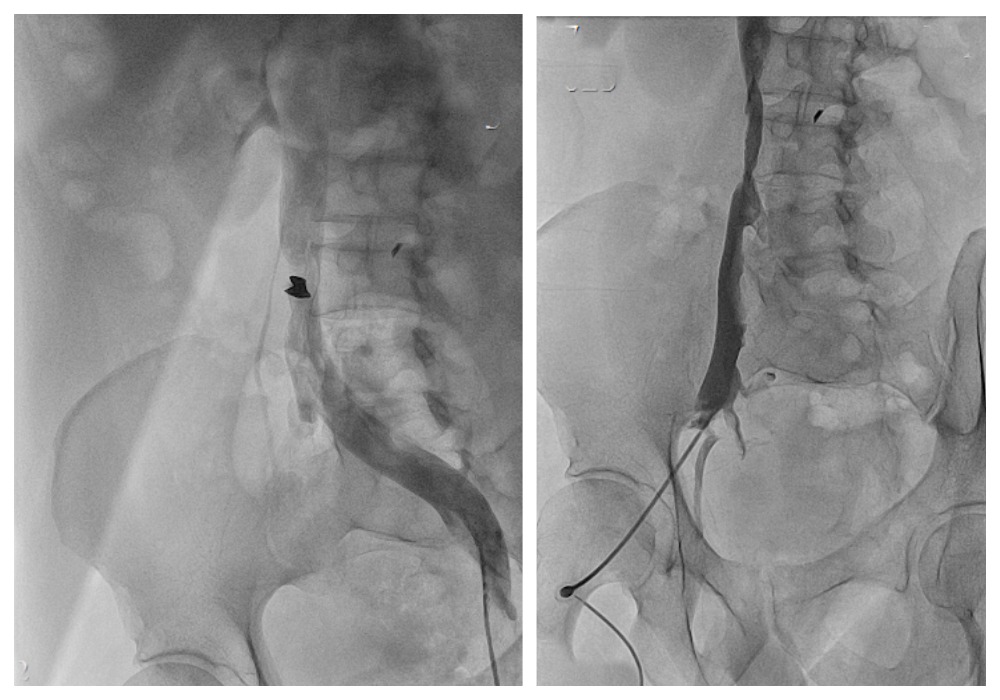

При обследовании, по данным КТ-ангиографии, флебографии, диагностирован осколок в нижней полой вене 20х15 мм, перекрывающий вену на ½ просвета.

Пациенту был поставлен клинический диагноз: сочетанное ранение головы, живота, конечностей. Огнестрельное осколочное проникающее ранение живота с повреждением нижней полой вены, оскольчатым переломом крыла подвздошной кости. Инородное тело (осколок) нижней полой вены.

Сосудистые хирурги госпиталя Вишневского провели операцию за короткое время и с минимальной кровопотерей. Они выполнили удаление инородного тела из нижней полой вены, протезирование нижней полой вены аутовеной.

Послеоперационный период протекал гладко, без осложнений. Послеоперационная рана живота без признаков воспаления заживала первичным натяжением. По данным контрольных обследований, осколок из нижней полой вены был извлечен полностью, пришитый протез нижней полой вены адекватно функционировал. На 5-е сутки после операции пациент был переведен обратно в неврологическое отделение для продолжения реабилитационного лечения.